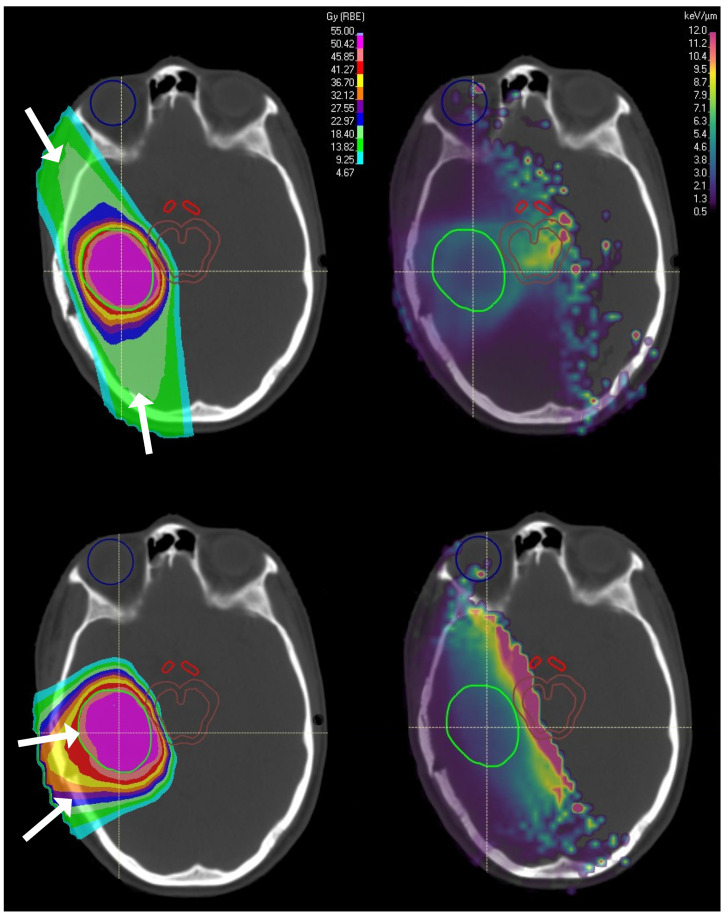

LET mapping in on the right in the below figure from

A Systematic Review of LET-Guided Treatment Plan Optimisation in Proton Therapy: Identifying the Current State and Future Needs

Say they optimize LET to minimize high LET areas in the brainstem, while achieving adequate "dose" to the target volume. This may change the LET distribution within the target volume, functionally changing effective dose within the target, or even require a different beam angle solution that increases lower doses to larger volumes of normal brain.

View attachment 390511

Thanks for the graphic, I like this one from a Physics World article:

It's probably important to keep in mind that high LET by itself isn't enough to cause injury, you need both high physical dose and high LET/RBE.

Allow me a dumb question

On first glance which one of these three do we prefer

Top Bottom